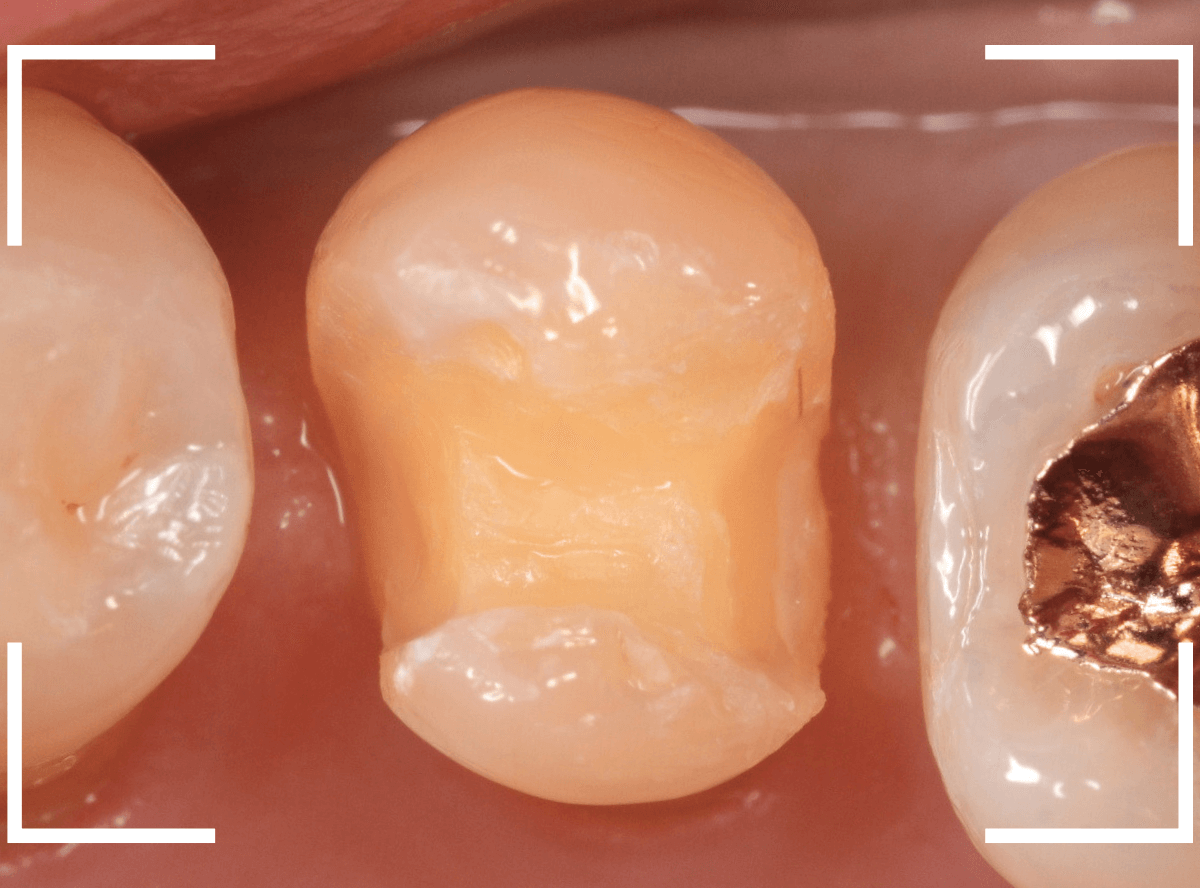

セラミックが精密にsetできるように、歯をトリミングします。

治療再開後、セラミックの最終修復を希望されましたので、歯をトリミングし、型取りします。

虫歯と歯のトリミング処置したところです。

歯をトリミングして、型を取ります。

できるだけ最小限に歯をトリミングして型を取ります。

型を取るために歯をトリミングします。

今回は、セラミックが割れた部分を少し厚みを出すように調整して型どりしました。

虫歯の治療後、最小限の形に整えて型を取ります。

改めて、歯の形を整えて型どりします。

ジルコニア・インレーが歯に綺麗にはまるように、形を整えて精密に型をとります。